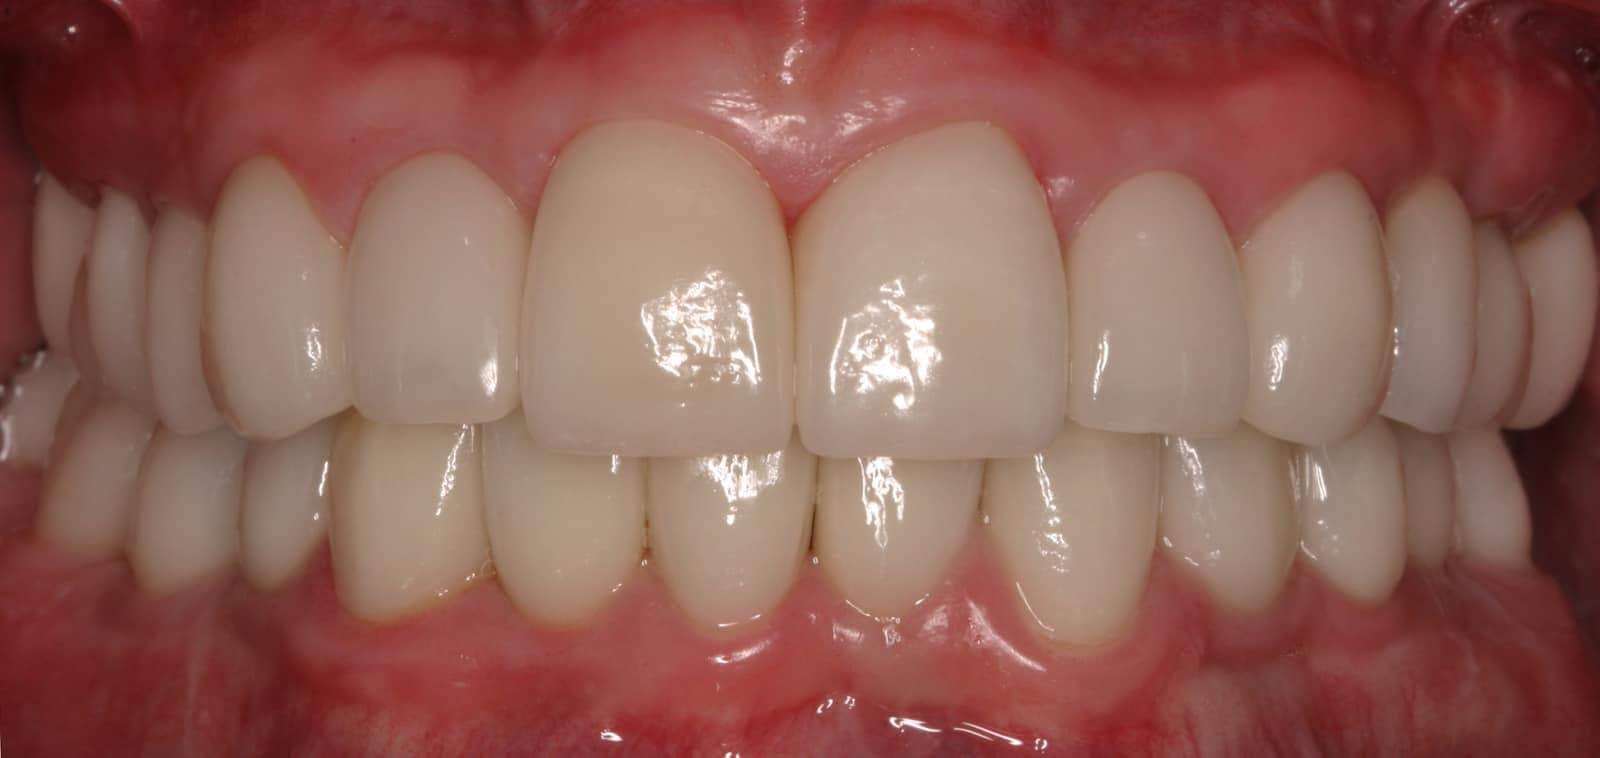

After:Â Implants were then placed by the team oral surgeon utilizing surgical guides fabricated by Dr. Leopardi. Dr. Leopardi then performed a complete dental (full mouth) rehabilitation: full coverage, conservative bonded porcelain restorations on natural teeth; all ceramic implant restorations on the upper lateral incisor implants (sited 7 and 10), porcelain fused to gold implant restorations on implants 3, 14, 19, 21, 23, 25, 28 and 29, at increased occlusal vertical dimension. Patient was restored to full function and aesthetics, significantly improving quality of life.